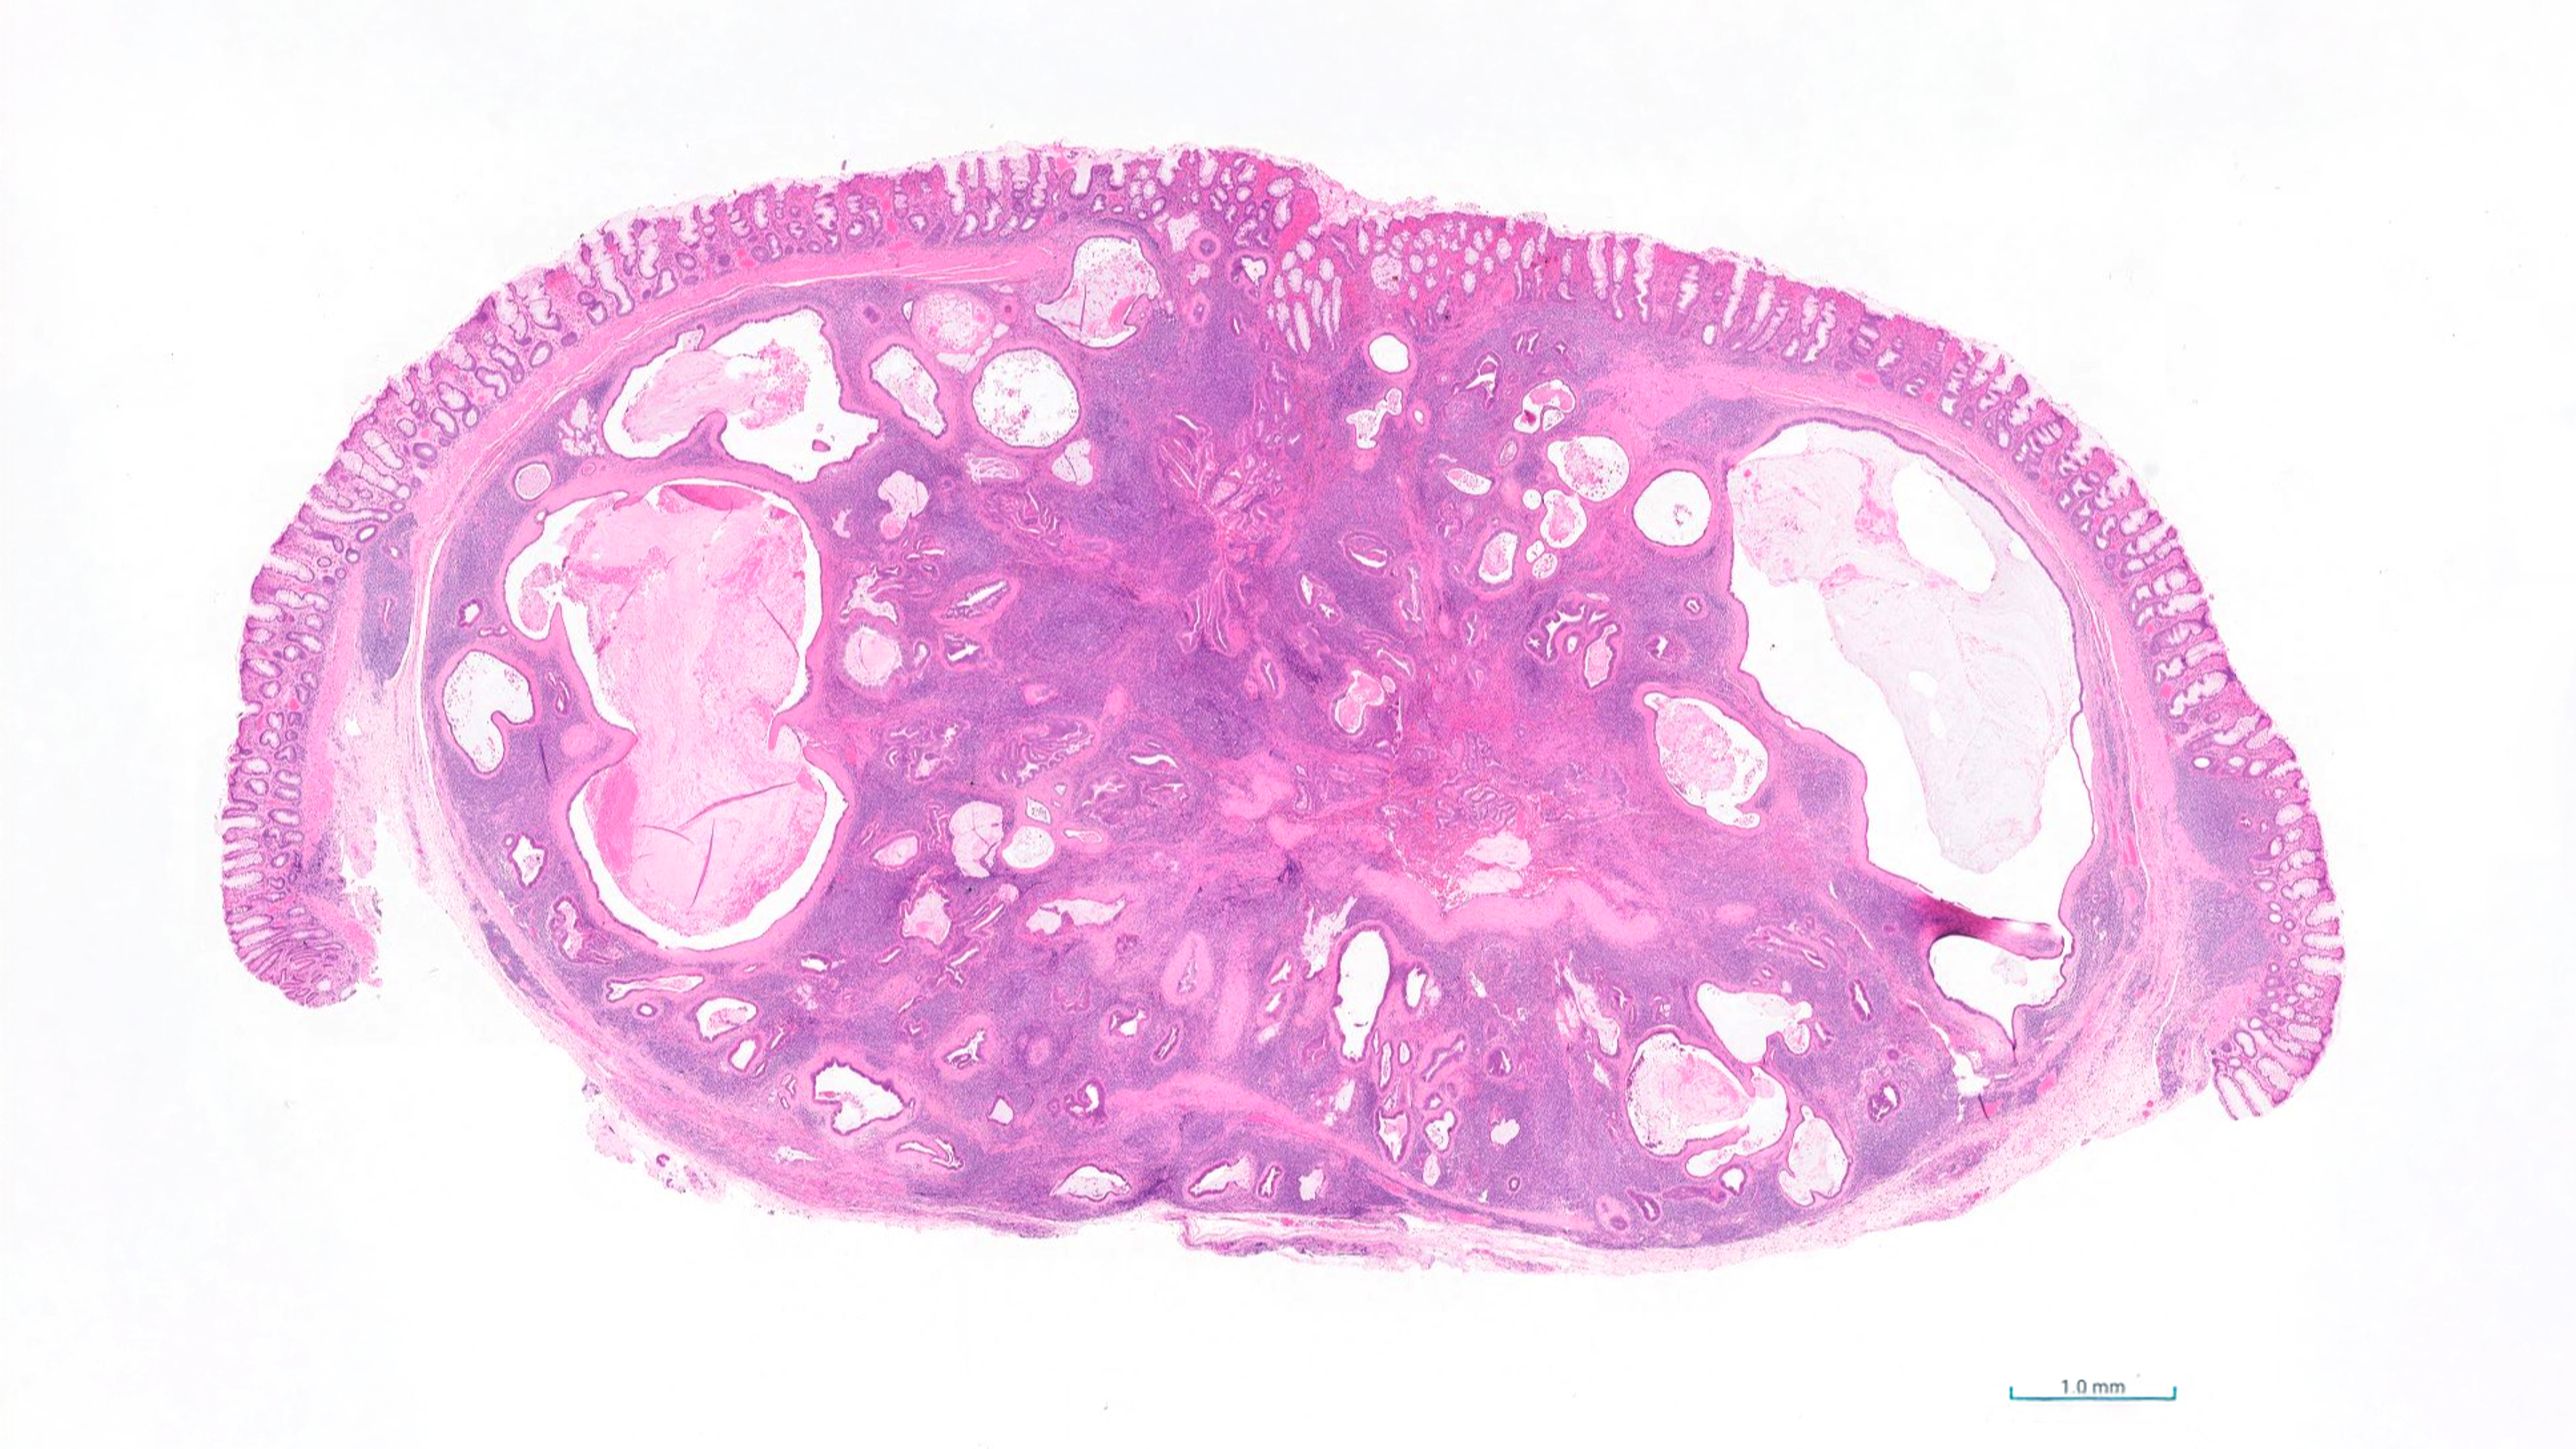

Organ: Rectum (segmental section)

History: This case was initially described as a rectal polyp in a dog and subsequently excised for histopathological evaluation. A firm intramural mass was detected during abdominal ultrasonography.

Macroscopic findings: The rectal wall contained a well-demarcated, firm, pale tan nodule measuring approximately 1.5 cm in diameter. The overlying mucosa was intact and smooth. On cut section, the lesion was homogeneous and lacked evidence of necrosis or cavitation.

Morphological diagnosis: Rectum: focal, well-demarcated, chronic nodular hyperplasia of lymphoglandular complexes.

Histopathology: The lesion consisted of well-organised lymphoid aggregates and follicles intimately associated with glandular profiles, some distended with mucus. No significant dysplasia, cellular atypia, or evidence of malignancy was observed. The architecture was consistent with a reactive process rather than neoplastic transformation.